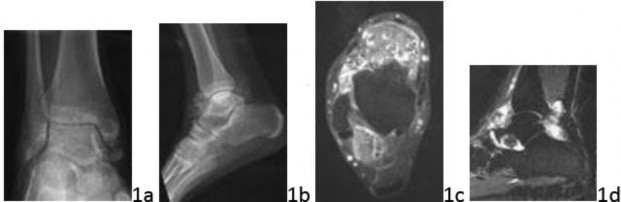

Question 3 Figures 3a through 3e show the radiographs and MRI scans of a 16-year-old boy. Which of the following best describes features of the patient's tumor?

Question 3 Figures 3a through 3e show the radiographs and MRI scans of a 16-year-old boy. Which of the following best describes features of the patient's tumor?

DISCUSSION: The imaging studies show a classic case of conventional high-grade osteosarcoma. Genetic alterations in the retinoblastoma gene and p53 tumor suppressor gene are common in this tumor. A translocation involving chromosomes 11 and 22 is characteristic of Ewing's sarcoma. Supernumerary ring chromosomes

are seen in parosteal osteosarcoma. Telomere translocations have been described in giant cell tumor of bone. A translocation of chromosomes X and 18 is typical of synovial sarcoma. The Preferred Response to Question # 3 is 5.